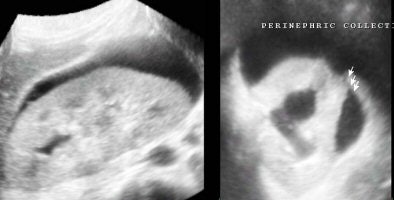

The volume contrast imaging (VCI) for thin-section viewing of structures (in 2-mm, 5-mm, or 10-mm slices) helps enhance the contrast between different planes, picking up subtle differences in margins of lesions or changes in outline.

| VCI images of 4-mm thickness show a small cortical break in the kidney (image on the right) with perinephric hematoma. |